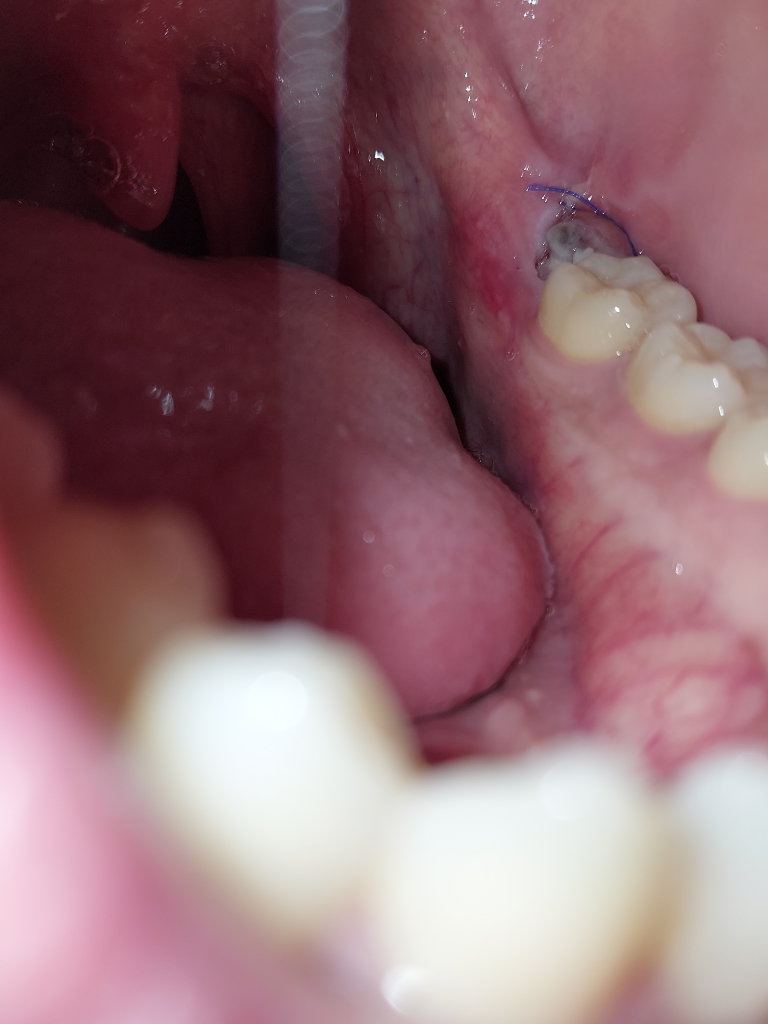

매복사랑니 발치한지 4일째인데 구멍이 조금 생겼습니다

발치한지 4일째 아침에 일어나서 잇몸상태를 보니 전날까진 보이지 않던 구멍이 보이더군요 정상적인 치유 과정인지 뭔가 잘못된건지 잘 모르겠습니다

오늘 상태

정상적으로 잘 낫고. 있습니다. 사진 상에서, 증상을 봤을 때 특별히 걱정하실 부분은 안보입니다.

발치 부위에 이가 빠지고 구멍이 생긴것으로 보입니다. 이는 정상적인 현상이며 잇몸은 시간이 지남에 따라 차오르게 됩니다. 잇몸이 차오르는 기간은 개인마다 차이가 있으며 3-6개월 이상 시간이 소요가 됩니다.

사랑니 발치하시고 실로 매꿔놓는건 잇몸이 봉인하는게 아니라, 음식물이 더 들어가라고 해놓은겁니다. 약간 구멍이 생겨도 크게 문제가 되지 않습니다.